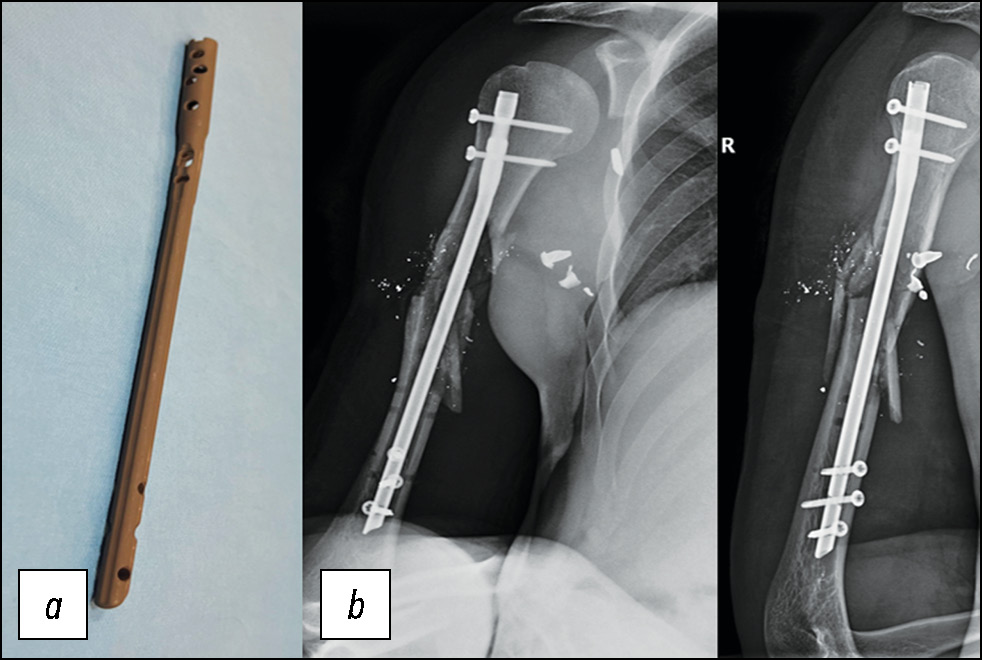

Рис. 8. Пациент 2: a — интрамедуллярный штифт с нанесённым путём микродугового оксидирования антибактериальным покрытием, b — контрольные рентгенограммы после остеосинтеза.

Fig. 8. Patient 2: a, intramedullary nail with an antibiotic coating applied via micro-arc oxidation; b, follow-up radiographs after osteosynthesis.

Раненый 29 лет, поступил с этапов медицинской эвакуации на вторые сутки после получения ранения с диагнозом «огнестрельное осколочное слепое ранение правого плеча с оскольчатым переломом средней трети диафиза плечевой кости». На 12-е сутки после ранения пациенту была выполнена закрытая репозиция: остеосинтез плечевой кости интрамедуллярным штифтом с блокированием и антибактериальным напылением с одномоментным наложением вторичных швов на рану (рис. 7–9).

Рис. 7. Пациент 2: a — внешний вид пациента с наложенным аппаратом внешней фиксации, b — рентгенограммы плечевой кости при поступлении.

Fig. 7. Patient 2: a, the patient with an external fixation device; b, radiographs of the humerus on admission.